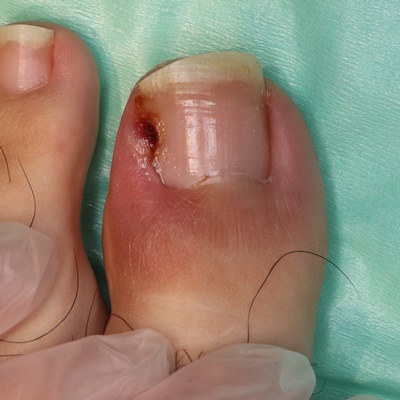

重度の陥入爪(不良肉芽形成あり)

1. 爪が食い込んで不良肉芽形成や潰瘍を形成している状態です。